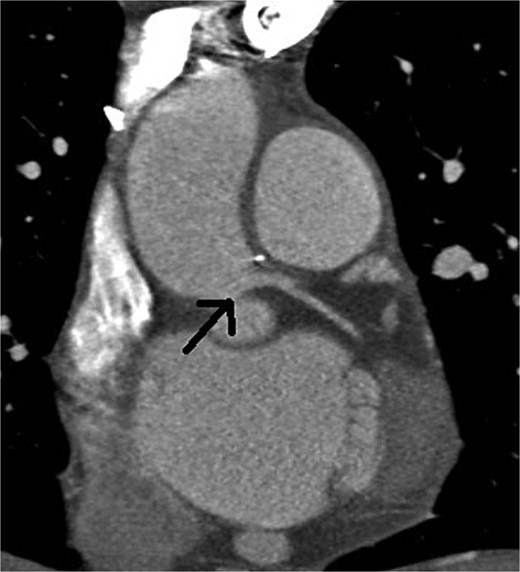

At the 5-month follow-up, repeated multislice computed tomographic coronary angiography confirmed widely patent left ostium, with no signs of recurrent stenosis (Fig. 3).

Postoperative multislice computed tomographic coronary angiography showing no signs of recurrent stenosis, with a widely open left main coronary artery (arrow)